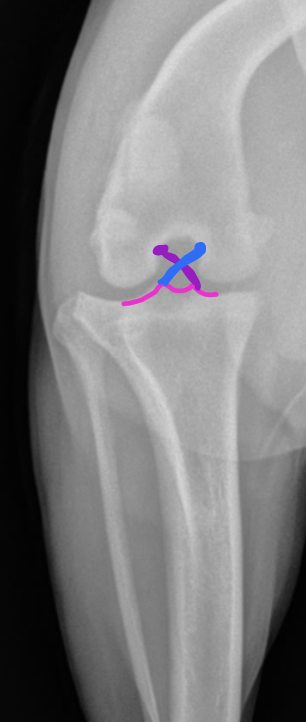

Q

Label the following colored structures

A

blue: smooth trochlear groove

pink: infrapatellar fat pad

red: patellar ligament

green: fascial planes

orange: femoral condyles